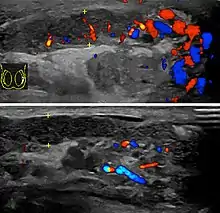

Epididimitis es un término médico que se refiere a una inflamación del epidídimo, la estructura tubular detrás del testículo donde maduran los espermatozoides y que conecta el testículo con los conductos deferentes.[1] Es un trastorno que resulta doloroso en varios grados y se suele acompañar con un enrojecimiento e hinchazón del escroto. La epididimitis es una de las causas más frecuentes de escroto agudo aunque rara vez puede ser una enfermedad crónica. Si el diagnóstico no se logra con la historia médica del paciente y su examen físico, un ultrasonido Doppler puede confirmar el aumento del flujo sanguíneo característico de un epidídimo inflamado.

Diagnóstico

La epididimitis puede ser difícil de distinguir de la torsión testicular. A veces, ambas circunstancias pueden ocurrir simultáneamente. Varias pruebas son necesarias para distinguir una situación crónica de epididimitis de una serie de condiciones clínicas que pueden causar dolor constante a nivel de la bolsa escrotal. Estas enfermedades son: cáncer de testículo, la inflamación de los nervios y los músculos puede causar o contribuir a la epididimitis crónica. Como último recurso, puede utilizarse la cirugía exploratoria.